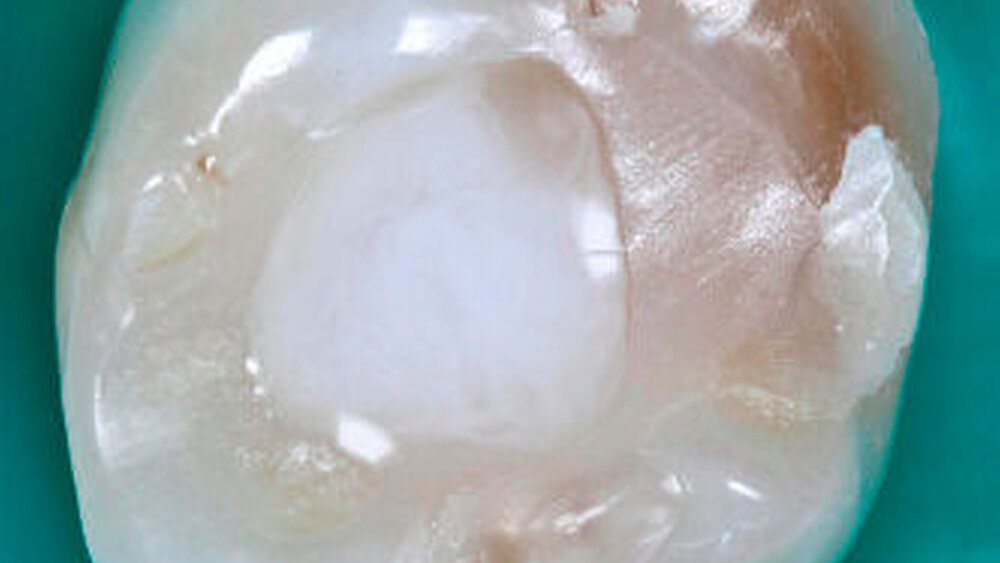

Beim direkten Kontakt zwischen CHX und NaOCl kommt es zur Ausfällung eines orange-braunen Präzipitats (Abbildung 1), das das Wurzelkanalsystem verunreinigt und somit die Wurzelkanal- behandlung erschwert. Dieses kann auch zur Herabsetzung der Dentinpermeabilität im apikalen Wurzeldrittel führen. Darüber hinaus besteht ein Verfärbungsrisiko des behandelten Zahnes. Ob das Präzipitat Parachlor- anilin (PCA) enthält, das beim Menschen ein toxisches und kanzerogenes Potenzial besitzt, wird zurzeit kontrovers diskutiert [Basrani et al., 2007; Prado et al., 2013]. Vor diesem Hintergrund empfehlen die Autoren eine Zwischenspülung. Hier stellt vermutlich reiner Alkohol die einzige Möglichkeit dar, die Präzipitation vollständig zu vermeiden.